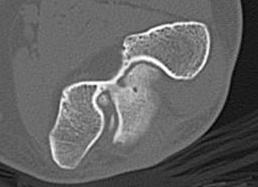

CT

Define olecranon and coranoid process osteophytes

Identification loose bodies

Osteophyte of the olecranon likely impinging in extension

CT demonstrating loose bodies in the ulnohumeral joint

Multiple loose bodies in anterior and posterior elbow joint